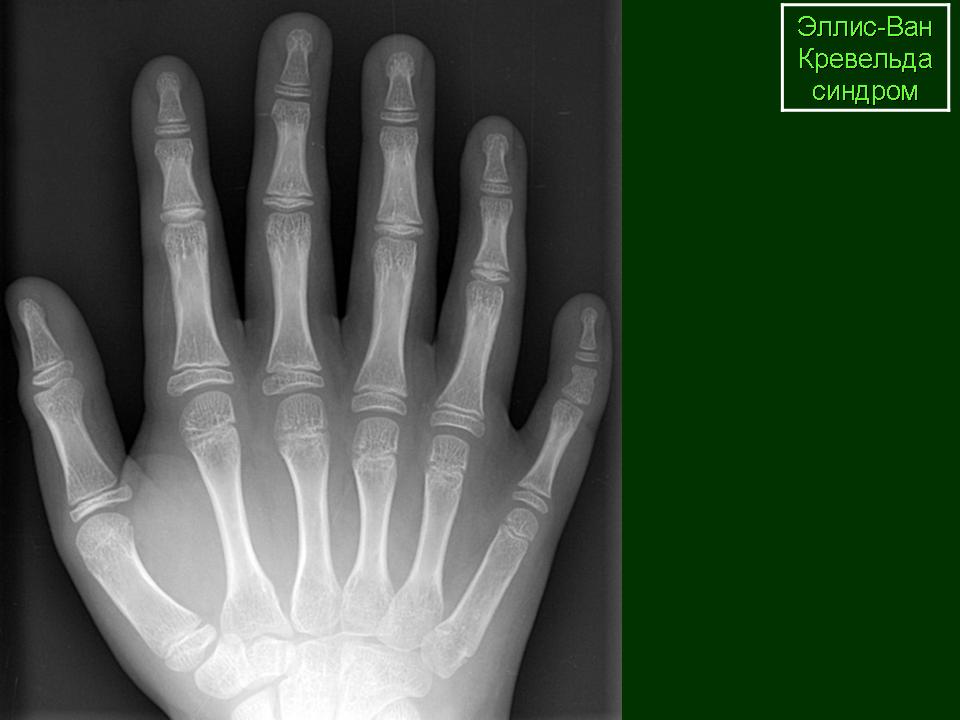

ЭЛЛИСА – ВАН КРЕВЕЛЬДА СИНДРОМ

(описан педиатрами – британским R. W. В. Ellis, 1902–1966, и нидерландским S. van Creveld, 1894–1971; синонимы – хондроэктодермальная дисплазия, мезоэктодермальная дисплазия) – наследственное заболевание: непропорциональная низкорослость, симметричное укорочение конечностей за счет предплечий и голеней, постаксиальная полидактилия кистей, иногда стоп, редкие, ломкие волосы или алопеция, гипоплазия или аплазия ногтей, частичное отсутствие зубов, мелкие, рано выпадающие зубы, короткая верхняя губа, расщелины губы и (или) нёба. Поражаются и внутренние органы: врожденные пороки сердца (дефект межпредсердной перегородки или ее отсутствие), пороки развития мочеполовой системы (крипторхизм, эписпадия). У части больных наблюдается умственная отсталость. Рентгенологически выявляют замедленное развитие ядер окостенения в длинных трубчатых костях, короткую грудную клетку, вальгусную деформацию голеней, множественные экзостозы, гипоплазию верхней латеральной части большеберцовой кости, трехзубчатую конфигурацию вертлужных впадин. Тип наследования – аутосомно-рецессивный. Лечение симптоматическое.